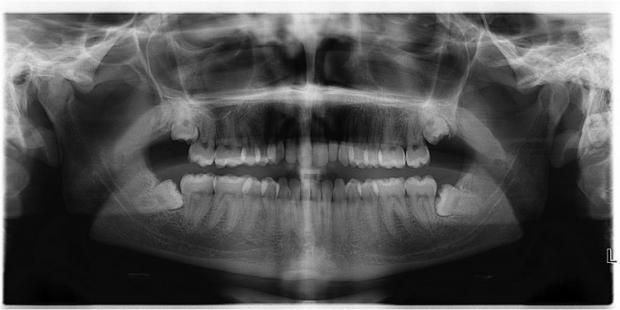

Chúng ta hoàn toàn có cơ sở để mà 'đổ lỗi' cho tổ tiên vì sự tồn tại của những chiếc răng khôn thích mọc lệch.

Cũng như những đặc tính thích nghi không xuất hiện trong 'một sớm một chiều', những đặc tính không còn cần thiết nữa cũng mất rất nhiều thời gian để có thể biến mất. Đối với con người, những đặc tính như vậy bao gồm ruột thừa, răng khôn và xương cụt.

Không giống như những thứ được thiết kế một cách thận trọng, sự tiến hóa của các loài vật không nhằm hướng đến sự hoàn mỹ, mà chỉ cần khả năng tự thích nghi là đủ. Hơn nữa, tiến hóa không thể bắt đầu từ hư không, mà luôn phải có điểm xuất phát cho tất cả các loài, và điều này dễ dẫn đến những đặc tính không còn cần thiết nữa từ tổ tiên bị sót lại (Như chuyện răng khôn thích mọc lệch chẳng hạn).